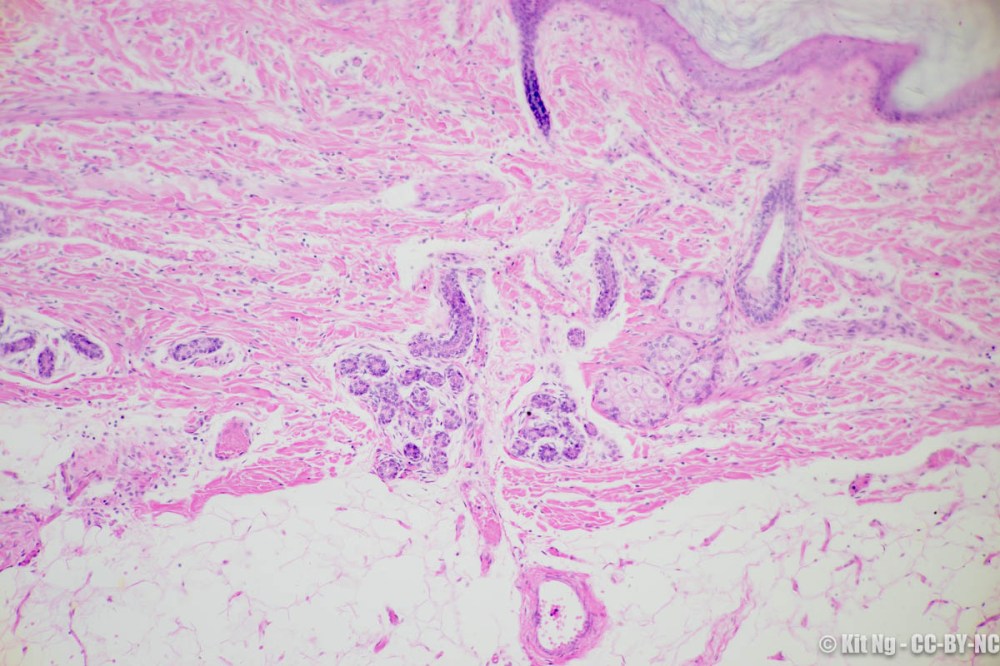

Eccrine sweat glands are the more common type of sweat glands and they can be found everywhere but predominantly on palms and soles. They are composed of both simple and stratified cuboidal epithelial cells. These glands secrete sweat that contains a high quantity of electrolytes and other metabolites.